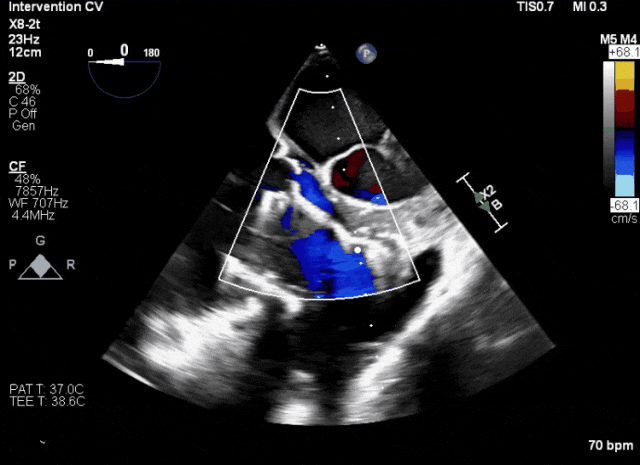

術(shù)后超聲顯示人工瓣膜穩(wěn)定性良好,瓣葉啟閉正常

術(shù)前超聲顯示三尖瓣重度反流合并拴系

術(shù)中TEE成像困難,偽影干擾

術(shù)后DSA、超聲顯示人工瓣膜穩(wěn)定性良好,瓣葉啟閉正常,無瓣周漏